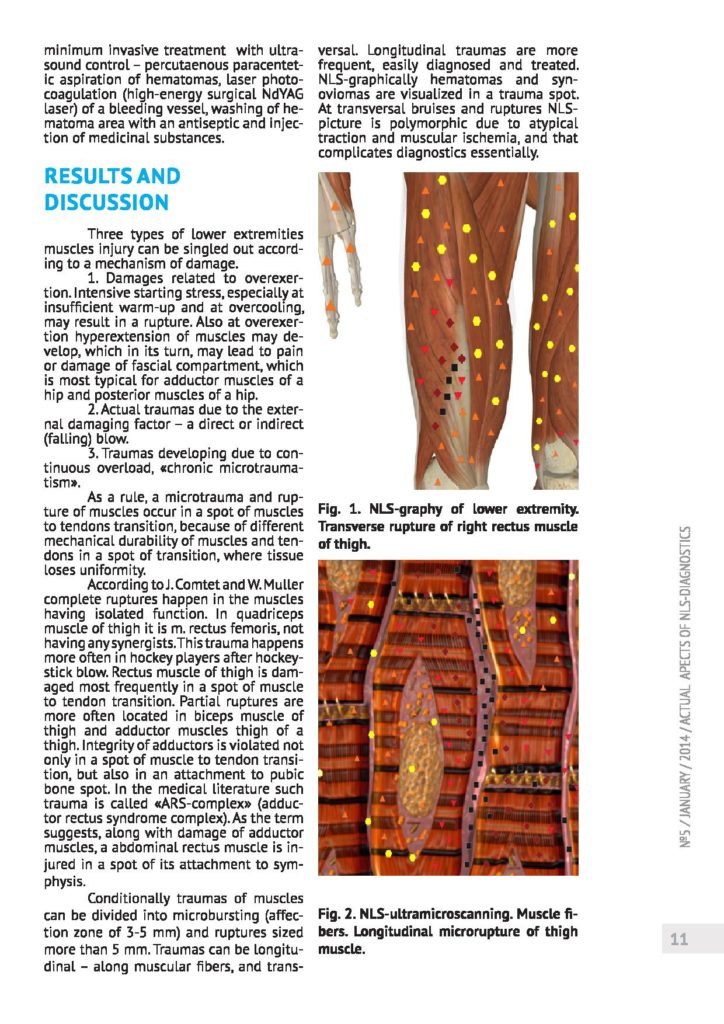

NLS - diagnostyka urazów mięśni u sportowców